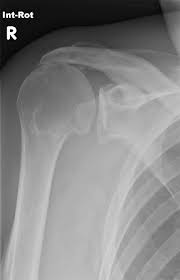

X-Rays

The imaging tests can visualize bone spurs. It also helps determine issues like arthritis. Your doctor can detect the potential cause of the pain using the technique.